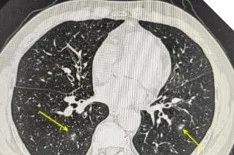

这种真菌感染的症状往往很隐蔽,患者多表现为咳嗽、咳痰、胸痛,很容易被当作普通的肺炎或咽喉炎来处理。肺部影像学也缺乏特征性改变,多类似于肺炎、肺结核或肺脓肿病变。正是因为这些症状、检查缺乏特异性,很多患者像张大爷一样,在确诊前经历了漫长的求医过程。